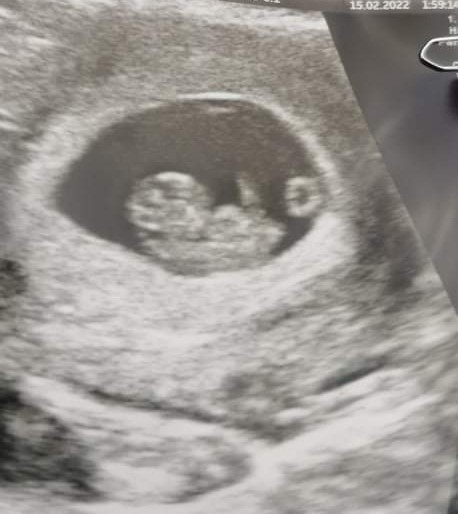

Er der nogle som har været til scanning omkring 8+3 som vil dele deres billeder? Jeg overvejer en scanning, men er nysgerrig på hvor meget man kan se, jeg var nemlig til en lige omkring uge 5

Husker ikke lige hvor langt men jeg er 8+ et eller andet

Vedhæftede fotos (klik for at se i fuld størrelse)

Vi var til scanning 7+5 og der var ikke rigtig andet at se end en blinkende klump Man kunne ikke se det lignede et barn. Var dog igen 2 uger efter, og der så vi tydeligt arme og ben, hoved osv.

Tusind tak for jeres svar, jeg synes man ka se meget på det billede der er lagt op her jeg har os kun uge 5 at sammenligne med som jo kun var en prik��